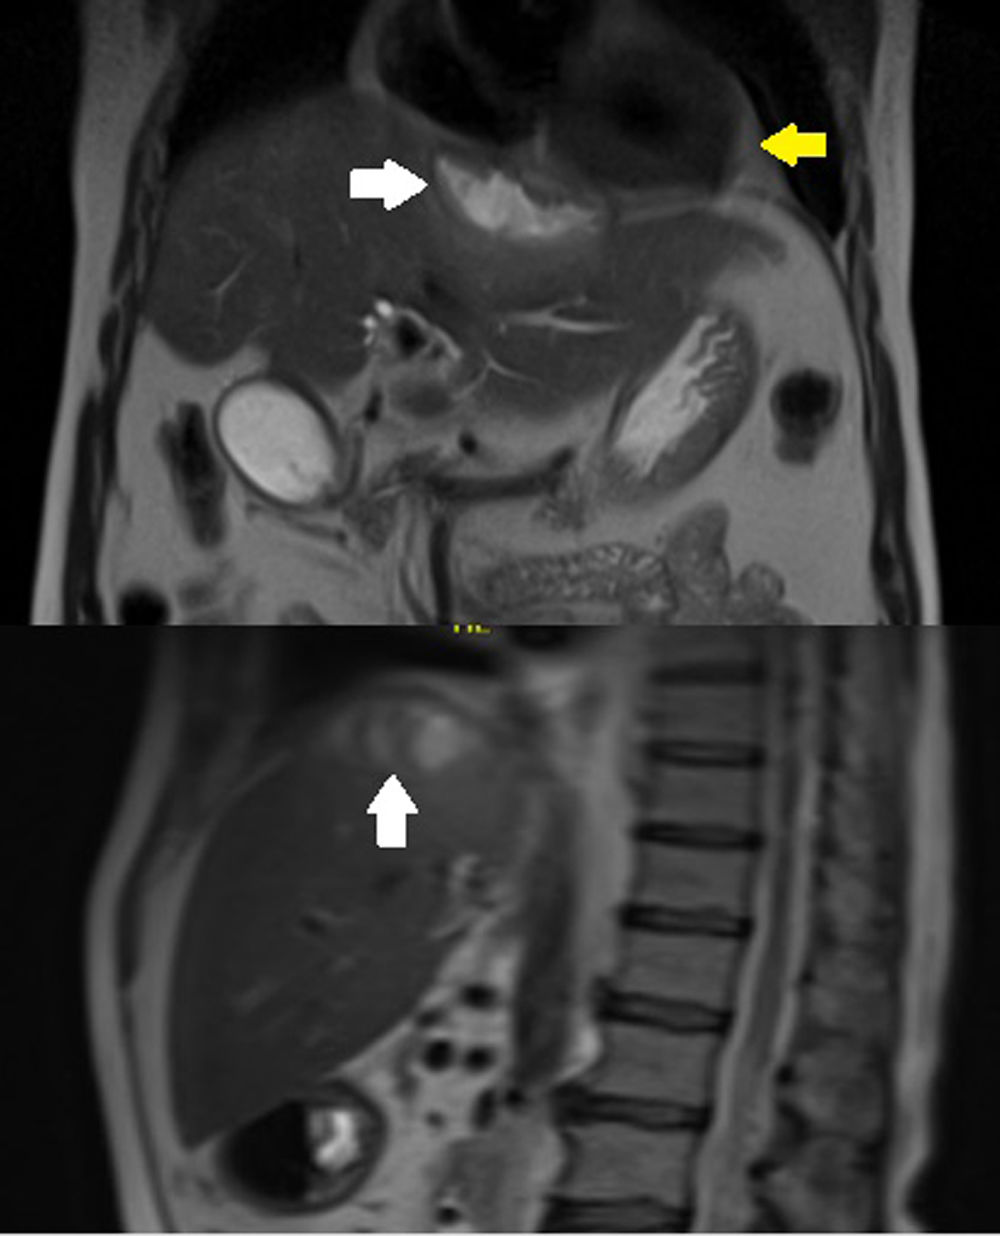

Case reportA 63-year-old male with arterial hypertension, who two years ago underwent an open cholecystectomy complicated by perforation of the gallbladder sac, was treated without apparent complications. During his follow-up with cholangio MRI, we found a 27 cc subphrenic collection adjacent to the IVa hepatic segment, which was treated with antibiotics because of its small size (Fig. 1).

(A) Simple CT of the chest showing residual pericardial effusion (white arrows) and pericardiocentesis catheter in the pericardial cavity (yellow arrows). (B) Subphrenic collection measuring 8cm×3cm×2cm with an estimated volume of 25cc (white arrow). Catheter in the pericardial cavity (yellow arrow). (C) Thinning of the diaphragm at the level of the collection and pericardial sac with apparent fistulous tract.